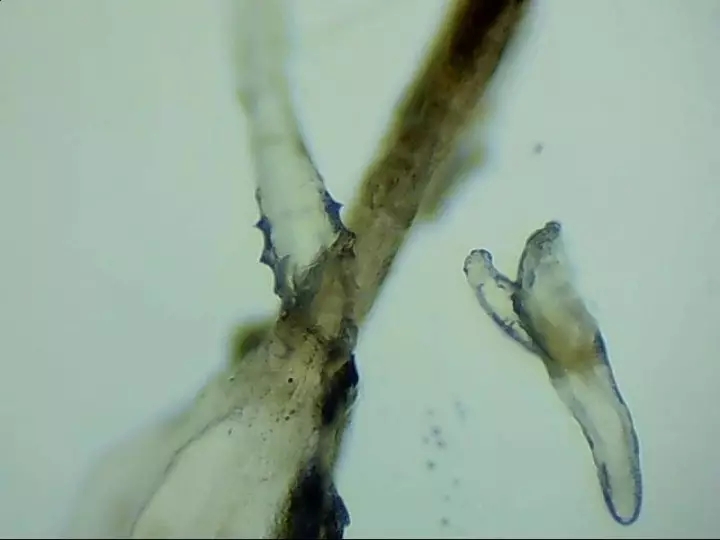

寄生在人體的蠕形螨以毛囊蠕形螨為主,皮脂蠕形螨次之。在眼部,毛囊蠕形螨寄生于睫毛毛囊,而皮脂蠕形螨則分布于睫毛毛囊的皮脂腺和瞼板腺內(nèi)。兩種螨蟲經(jīng)常生活在睫毛和眉毛根部,它們通過生產(chǎn)的卵、排泄的廢物和分泌的分泌物導(dǎo)致過敏反應(yīng),并在人體免疫系統(tǒng)變?nèi)鯐r引起眼部感染。

蠕形螨性瞼緣炎門診配備有光學(xué)顯微鏡鏡檢、活體激光共聚焦顯微鏡檢查等高新設(shè)備可作出精準(zhǔn)診斷。并有多種治療手段全方面驅(qū)逐、殺死螨蟲。